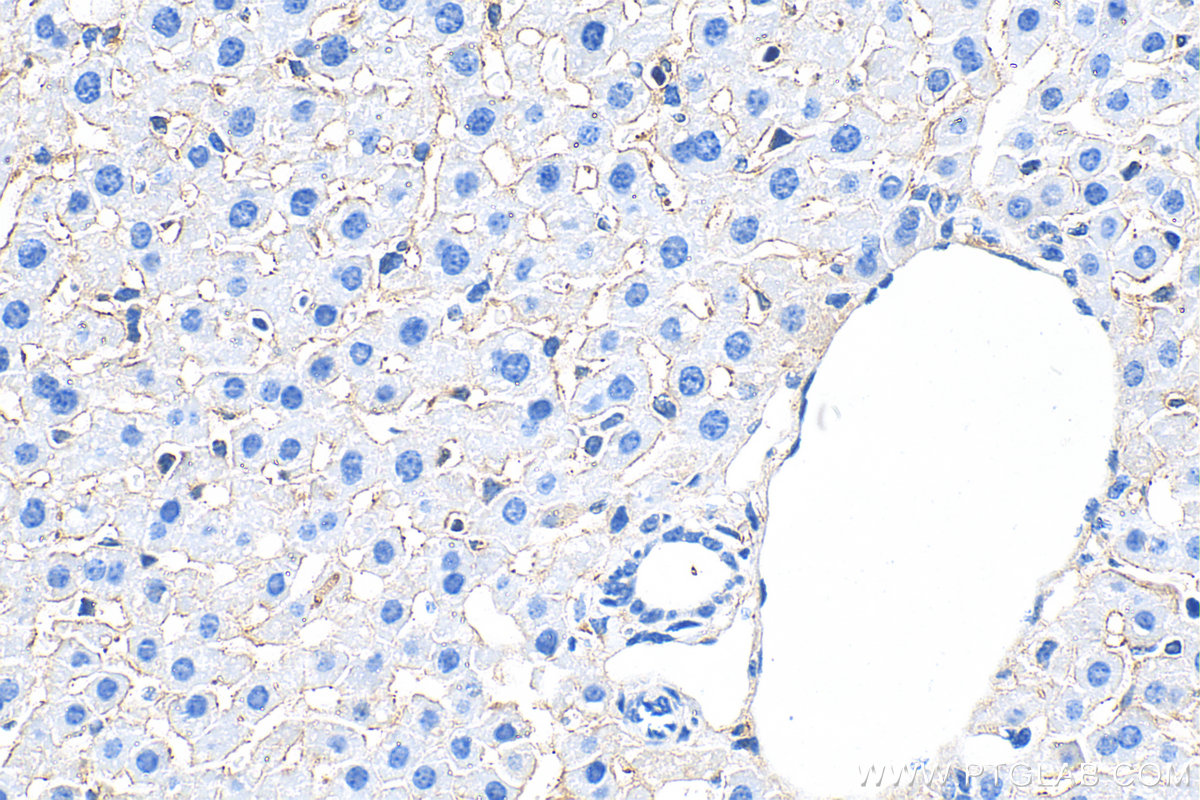

| Positive IHC detected in | mouse liver tissue Note: suggested antigen retrieval with TE buffer pH 9.0; (*) Alternatively, antigen retrieval may be performed with citrate buffer pH 6.0 |

| Immunohistochemistry (IHC) | IHC : 1:200-1:800 |